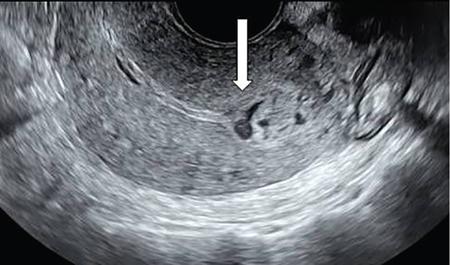

Venkatraman Indiran Bridging vessel sign Multiple vascular channels (white arrows) connecting uterus (black arrow) to an adjacent pelvic mass on imaging studies, is known as the ‘bridging vessel’ or ‘bridging vascular’ sign. Originally described on colour Doppler imaging, but also seen on computed tomography (CT) or magnetic resonance imaging (MRI). Helps in differentiating a mass of uterine origin, typically a subserosal fibroid, from other pelvic masses. Sensitivity and specificity of ‘bridging vessel sign’ in identifying subserosal fibroids range from 90% to 100%. (Best seen when subserosal fibroid is larger than 3 cm in diameter.) Ovarian masses invading the uterus may rarely produce a falsely positive bridging vessel sign. Broccoli sign Submucosal uterine leiomyoma prolapsing into the endocervical canal, along with its stalk in the uterine cavity on sagittal T2-weighted images together is called as ‘broccoli sign’ (white arrow). Submucosal uterine leiomyoma Bunch of grapes Intrauterine mass with cystic spaces without any associated foetal parts on ultrasound (white arrows) classically gives a ‘snow storm’ or ‘bunch of grapes’ appearance. Complete hydatidiform mole Hourglass sign Deep infiltrating endometriosis (DIE) affecting the posterior urinary bladder wall, usually in the midline, causes loss of its distensibility, resulting an hourglass configuration of urinary bladder. Deep infiltrating endometriosis (DIE) Hyperechoic line sign Normal endometrium surrounding the endometrial polyp on ultrasound appear as a hyperechoic rim on transvaginal ultrasound is called as ‘hyperechoic line sign’. Hyperechoic line sign represents a focal intracavitary lesion. Endometrial polyp Indian head dress sign/moose antler sign In deep infiltrating endometriosis (DIE), adhesions between the anterior wall of rectosigmoid and posterior wall of uterus, stretches the muscular layer of the bowel and creates an infiltrative nodule with parallel lines that extend from the adhesion to the rectosigmoid. This is called as ‘Indian head dress sign/moose antler sign’ (white arrow). This is seen on sagittal T2-weighted images as well as transvaginal ultrasound. Deep infiltrating endometriosis (DIE) Interstitial line sign An echogenic line that extends into the upper regions of the uterine horn and borders the margin of the intramural gestational sac is called as the ‘interstitial line sign’ (white arrow). Seen best on transabdominal/transvaginal ultrasound. Specific finding of interstitial pregnancy Mushroom cap sign Mushroom-shaped lesion which is seen displaced into the bowel lumen in patients with solid invasive endometriosis of the rectosigmoid colon on axial or sagittal T2-weighted MRI is called as ‘mushroom cap sign’ (red box and white arrow). Low signal intensity base of the mushroom corresponds to hypertrophy and fibrosis of the muscularis propria, whereas the high intensity cap represents oedematous mucosa and submucosa. Deep infiltrating endometriosis (DIE) Pedicle artery sign Feeding vessel sign Central vessel entering the endometrium from the surrounding myometrium colour Doppler imaging of the endometrium in endometrial polyps is called as pedicle artery sign (white arrow). Endometrial polyps in women with postmenopausal bleeding. (Sensitivity of 76.5%; specificity of 95.3%.) Popcorn ball calcification Dense, amorphous calcifications of uterine fibroids seen on the plain radiographs is called as ‘popcorn calcification’ (white arrow). Confluent, coarse calcification constitutes the most specific radiographic sign of a benign uterine fibroid; but only 10% or fewer of fibroids show calcification. Question mark sign of uterus The uterine corpus that is flexed backward with the fundus of the uterus facing the posterior pelvic compartment and the cervix directed anteriorly toward the urinary bladder, is called as question mark sign of uterus (white arrow). Also called as comma-shaped uterus. 93% specificity and 75% sensitivity in diagnosing adenomyosis uterus. Sliding organs’ sign When the uterus and ovaries glide freely over the posterior and anterior organs (such as rectum and urinary bladder, respectively) during real-time dynamic transvaginal sonography, it is called as ‘positive sliding organs’ sign’. In case of adhesions due to endometriosis, free gliding of organs is absent and is called as negative sliding sign. Snowstorm sign Grainy appearance with low-level homogeneous internal echoes which move slowly downward due to their viscosity seen in endometrioma on transvaginal ultrasound is called as snowstorm sign. Endometriomas Split fibre sign Presence of curvilinear T2 hypointense strands within the degenerated leiomyoma separated by the fluid accumulation and oedema is called as the ‘split fibre’ sign. Split fibre sign on T2-weighted MRI can be used to differentiate hydropic degeneration from other conditions like malignant change. Three-line sign or triple line sign or trilaminar appearance Shortly before ovulation, two additional bright linear echoes outline two hypoechoic layers of endometrium with a central hyperechoic line in the endometrium (white arrow). It is called as the ‘three-line sign’ or ‘triple line sign’ or trilaminar appearance. A triple-line pattern with a moderate endometrial thickness is associated with a good clinical outcome on in-vitro fertilization. Venetian blind shadowing Also known as ‘rain shower’ appearance Heterogeneous myometrial appearance due to hyperechoic heterotopic endometrial tissue and hypoechoic hyperplastic smooth muscle appearing as vertical linear bands of shadows on ultrasound is called as ‘Venetian blind shadowing’. Classically described in uterine adenomyosis; sometimes in uterine fibroids also. Bead on strings sign Thickened endosalpingeal longitudinal folds within a dilated fallopian tube without wall thickening appears as small mural nodules on cross-sectional images on ultrasound is called as ‘bead on strings’ appearance. Seen in chronic salpingitis Beaded tube Multiple constrictions along the course of fallopian tube may form due to scarring is seen in genitourinary tuberculosis and shows a ‘beaded’ appearance. Female genital tuberculosis Cogwheel sign Thickened endosalpingeal longitudinal folds within a dilated fallopian tube with thickened wall appears as small mural nodules on cross-sectional images across the long axis of the fallopian tube on ultrasound (white arrows) produce a characteristic ‘cogwheel’ appearance. Seen in acute salpingitis. The presence of thickened longitudinal folds is pathognomonic for hydrosalpinx. Cobblestone tube Rounded filling defects in cases of fallopian tube tuberculosis are called as the cobblestone pattern. Is an effective radiographic sign of intraluminal scarring and adhesions. Female genital tuberculosis Golf club tube Occlusion of the isthmus or fimbrial end of the fallopian tube and filling up of the tube with serous or clear fluid produces a moderate dilatation at the fimbrial end, produces a ‘golf club–like appearance’. Female genital tuberculosis Halo sign Thin radiolucency seen separating the loculated peritubal collection from the dilated tube, is known as the ‘halo sign’. This radiolucent halo represents the thickened wall of the tube. Female genital tuberculosis Incomplete septation sign Thin linear structures appearing to protrude into the tubular cystic adnexal structures, but not touching the opposite walls is called ‘incomplete septation sign’ of hydrosalpinx. Apparent septae are due to apposition of the inner walls of the dilated and folded fallopian tube. Hydrosalpinx Pipe stem tube Rigid contour of the fallopian tube seen in cases of fallopian tube tuberculosis is called as ‘pipe stem appearance’. Female genital tuberculosis Leash sign Typical eccentric leash of vessels on colour Doppler (white arrow) showing a low resistance placental type of flow on spectral Doppler in fallopian tube ectopic pregnancies is called as leash sign.